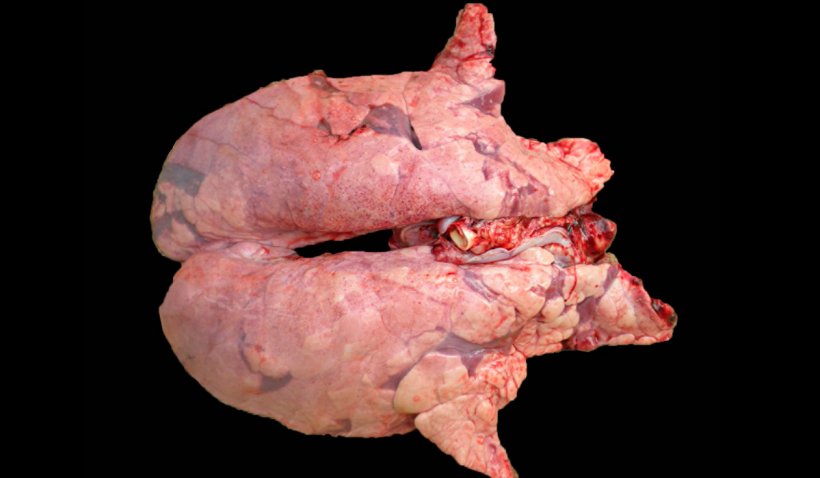

L'une des co-infections les plus fréquentes dans les élevages porcins en cas de CRP est causée par M. hyopneumoniae et le SDRPv (figure 2). Dans les cas où cette co-infection a été diagnostiquée, une corrélation positive a été observée entre les animaux séropositifs pour chacun des deux agents, c'est-à-dire que la plupart des animaux positifs pour le SDRPv sont également positifs pour M. hyopneumoniae. En outre, il a été constaté que M. hyopneumoniae prolonge et augmente la pneumonie produite par le SDRPv, ce qui pourrait être dû au fait que chez les animaux co-infectés par les deux agents pathogènes, il y a une augmentation des cytokines pro-inflammatoires, telles que IL1-β, IL-8 et TNF-α, qui augmentent la réaction inflammatoire au niveau pulmonaire, mais aussi une augmentation de la synthèse de l'IL-10, qui est une cytokine anti-inflammatoire qui inhibe et module la production d'autres cytokines et qui permettrait de perpétuer les dommages au niveau pulmonaire en empêchant le déclenchement d'une réaction inflammatoire incontrôlée. L'IL-10, à son tour, est également capable de moduler la réponse immunitaire de l'animal, ce qui, avec l'activation d'autres mécanismes, modifie la réponse immunitaire adaptative, permettant à l'agent pathogène de continuer à exercer son action dans les poumons pendant plus longtemps.

Figure 2. Poumon d'un porc co-infecté par M. hyopneumoniae et le SDRPv. Poumon non affaissé avec des zones de lésions rouge-brun réparties dans tout le parenchyme, lésions typiques du SDRP, qui présentent, en même temps dans les zones cranioventrales, des zones de consolidation, de couleur rougeâtre, produites par l'infection à M. hyopneumoniae.